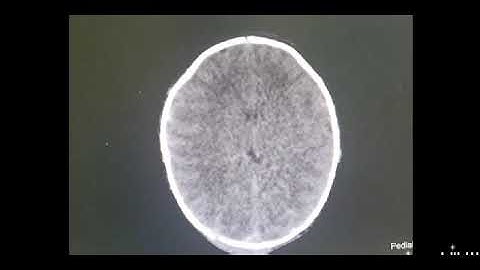

Can Epidural Hematomas Occur In Children? - The Operating Table